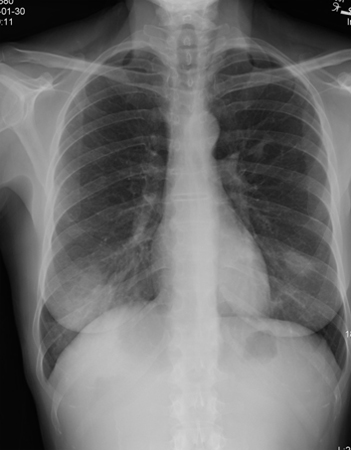

Radiografia torácica mostrando infiltrados irregulares bilaterais

Do acervo de Gary R. Epler, MD